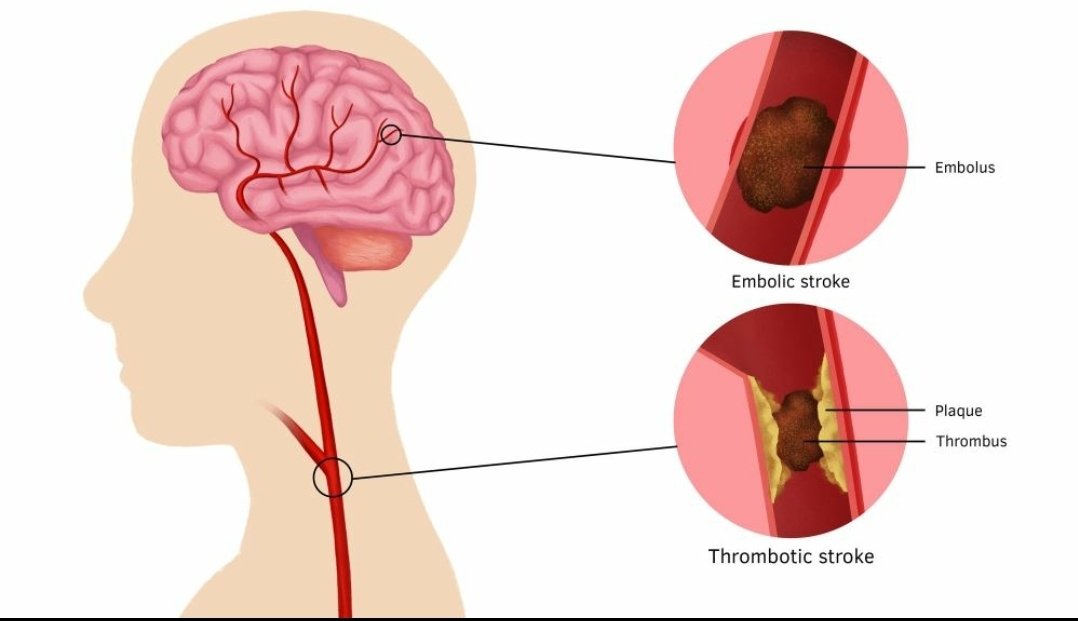

💥هي نقص ترويه الدم (الاوكسجين) لمنطقه بالمخ اوالحبل الشوكي اوشبكية العين

💥انواعها(اقفاريه ونزفيه)

💥اسبابها

🧠 انسداد في الشرايين (#السكته_الدماغيه_الاقفاريه)

بسبب #خثرة مثلا

🧠 انفجار الشرايين (#سكته_دماغيه_نزيفيه)

🧠انسداد #الاورده وتوقف الدورةالدمويه بالمنطقه

#السكته_الدماغيه_الاقفاريه

💥هي نقص في ترويه الدم للمخ اوالحبل الشوكي اوشبكيةالعين

💥بسبب (انسداد أو تضيق) في شرايين(القلب،الرقبه،الراس) الموصله للدم او الاورده المصرفه

💥انواعها

🧠عابرة(مؤقته)

اقل من ٢٤ ساعه و لاتظهر في الاشعات

🧠دائمه

تستمر اكثر من ٢٤ ساعه او تظهر في الاشعات